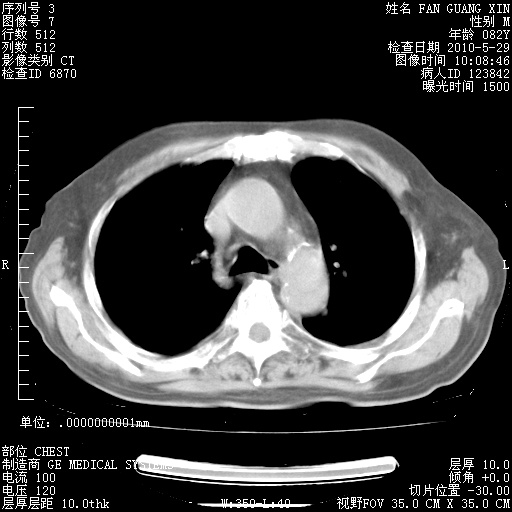

再治疗10天后的肺部CT

再治疗10天后的肺部CT 纵膈窗

阅读此次胸部CT,肺间质渗出性改变较入院时有吸收。目前从体温、白细胞、中性分叶明显增高,肯定存在细菌感染(发生医院感染哦,若无消化道及泌尿系统等感染的依据,肺部感染可能大)。若你院头孢哌酮舒巴坦钠耐药率较高,同意你的方案,若48小时体温仍高,可考虑使用碳青霉稀类抗菌药物,同时可予超声雾化、注意滴数时加大液体量。白蛋白33.30g/L较低哦,需加强营养等支持治疗。